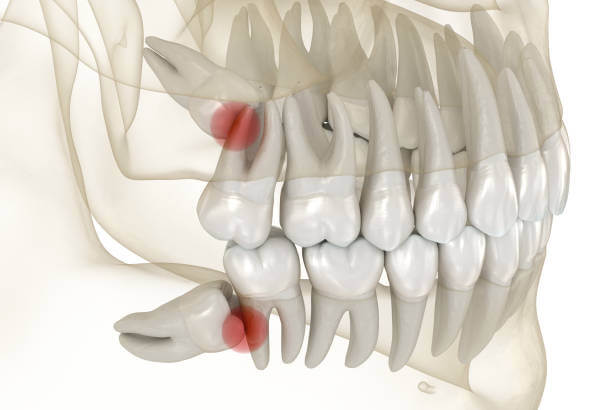

때때로 사랑니가 뼈에 묻혀서 그 주위에 낭종과 같은 것을 일으켜 뼈를 손상시키기 때문에 사랑니를 발치하는 경우가 많습니다. 그러나 사랑니는 뼈가 잘 발달되어 있고 잇몸으로 덮여 있지 않다면 발치 할 필요가 없다고 합니다.

드라이소켓은 사랑니 발치 후 제대로 치유되지 않아 붓거나 염증이 발생하면서 통증이 나타날 수 있습니다. 사랑니 발치 후의 대표적인 부작용으로는 상처 치유 과정에서 혈전이 제대로 형성되지 않거나, 형성되더라도 3일 이내에 제거되어 사랑니 아래 잇몸뼈가 그대로 노출됩니다.

잇몸이 노출되면 입안에 남아있던 세균이 침투해 염증을 일으켜 심한 통증을 유발할 수 있습니다. 또한 잇몸의 경우 다른 신체 조직과 달리 딱지가 한번 빠지면 다시 형성되기 어려우므로 사랑니 발치 후 드라이소켓이 의심된다면 빠른 시일 내에 치과에서 봉합하는 것이 필요합니다.